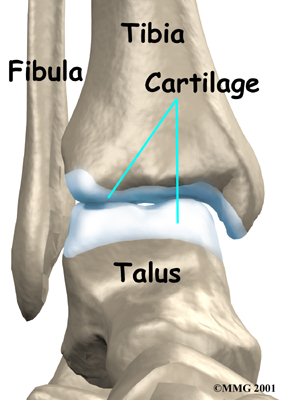

The ankle joint is made up of three bones: the lower end of the tibia (shinbone), the fibula (the small bone of the lower leg), and the talus (the bone that fits into the socket formed by the tibia and fibula). The talus sits on top of the calcaneus (the heelbone).

Inside the joint, the bones are covered with a slick material called articular cartilage. Articular cartilage is the material that allows the bones to move smoothly against one another in the joints of the body.

The cartilage lining is about one-quarter of an inch thick in most joints that carry body weight, such as the ankle, hip, or knee. It is soft enough to allow for shock absorption but tough enough to last a lifetime, as long as it is not injured.